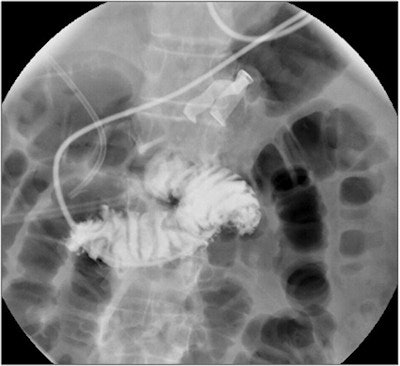

"The reason [retained surgical items] are so often missed even by skilled radiologists, we believe, is because their radiopaque (x-ray visible) elements or filaments are deformable and are not standardized across vendors," Marentis said. "Their shape changes and creates a perceptual barrier for the radiologist, who may misinterpret the finding as a garment or external to the patient. A large part of the problem is the defective nature of surgical sponges and towels as highly variable detection targets."

Seeking to improve on this situation, the University of Michigan team developed a method that employs microtags and CAD software. Codeveloped with the Chronis Lab in the university's bioengineering department, the microtag is visible on radiographs, doesn't change its shape, avoids high-contrast anatomical features, and produces a similar 2D projection regardless of orientation in space, Marentis said.

CAD software codeveloped with the department of radiology's CAD Research Laboratory then detects the microtags on radiographs using machine learning techniques. The CAD system includes six task-based processing modules for preprocessing, target enhancement, candidate labeling, segmentation, feature analysis, and classification. Detected tag locations are then highlighted on the radiographs for the radiologist to review.